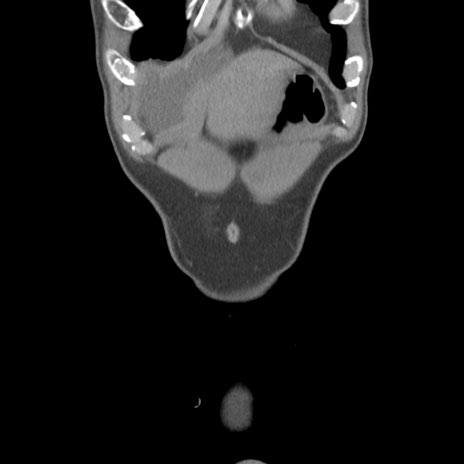

症例56 CT(冠状断像)

脂肪ウインドウ